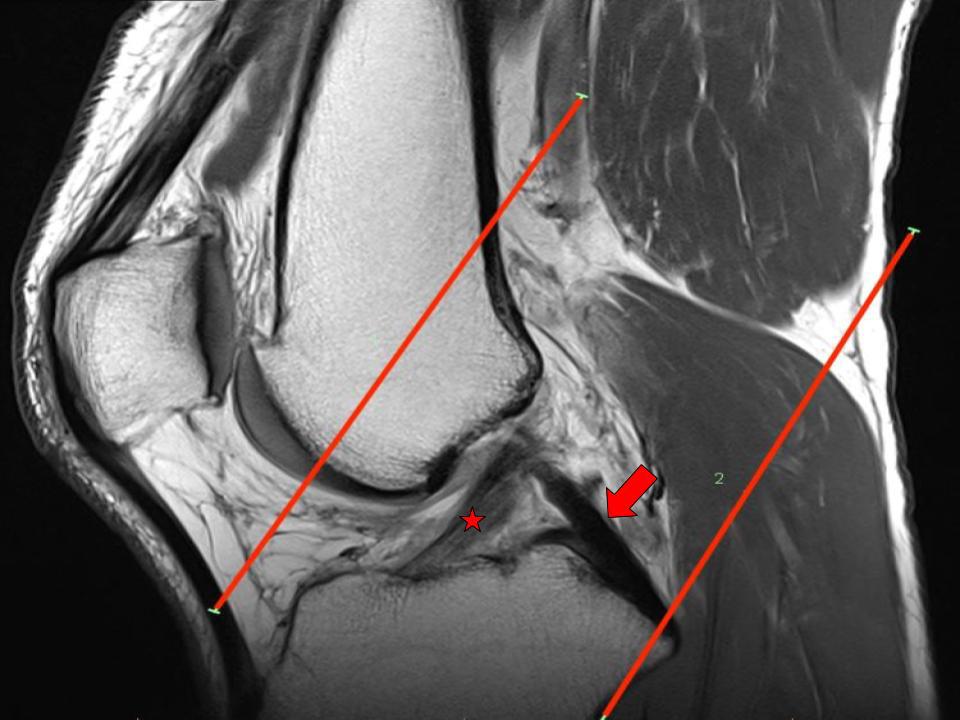

Atypical Scan Angles in Musculoskeletal MRI Radsource Blumensaat S Line Anatomic mpfl femoral guide pin location is just anterior to the intersection of the posterior femoral cortical line and blumensaat’s line on the. Minimally invasive medial collateral ligament (mcl) augmentation technique. Surgical reconstruction of the anterior cruciate ligament (acl) can be complicated by incorrect and variable tunnel. Posterior to blumensaat's line (b) (quoted from ladvas et al., 2012). The femoral. Blumensaat S Line.

Atypical Scan Angles in Musculoskeletal MRI Radsource Blumensaat S Line Surgical reconstruction of the anterior cruciate ligament (acl) can be complicated by incorrect and variable tunnel. The femoral deep mcl insertion is identified. Minimally invasive medial collateral ligament (mcl) augmentation technique. The following standardised technique was employed to ensure accuracy. On the sagittal plane of the mri the front border of the tibial tunnel should. Posterior to blumensaat's line (b). Blumensaat S Line.